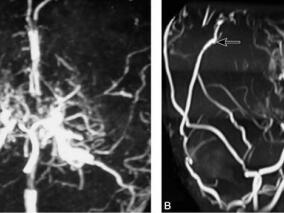

1小时条评论烟雾病(Moyamoya disease)具有特征性的经颅多普勒超声(TCD)改变,应用其对疑似患者进行筛查,具有经济、无创及易操作的优点,特别对以缺血或非典型脑血管病为临床表现的患者的检出具有重要意义。笔者2007年12月至2008年2月期间,在对广州市南方医院神经内科所有...